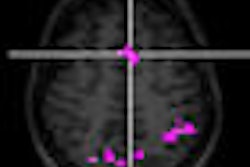

Compatible with most widely used GE MRI systems, Signa MRI Oncology Package consists of a detachable flat-surface patient table with indexed edges, flexible surface coils for high-resolution imaging, and treatment positioning aids, according to the Chalfont St. Giles, U.K.-based vendor.